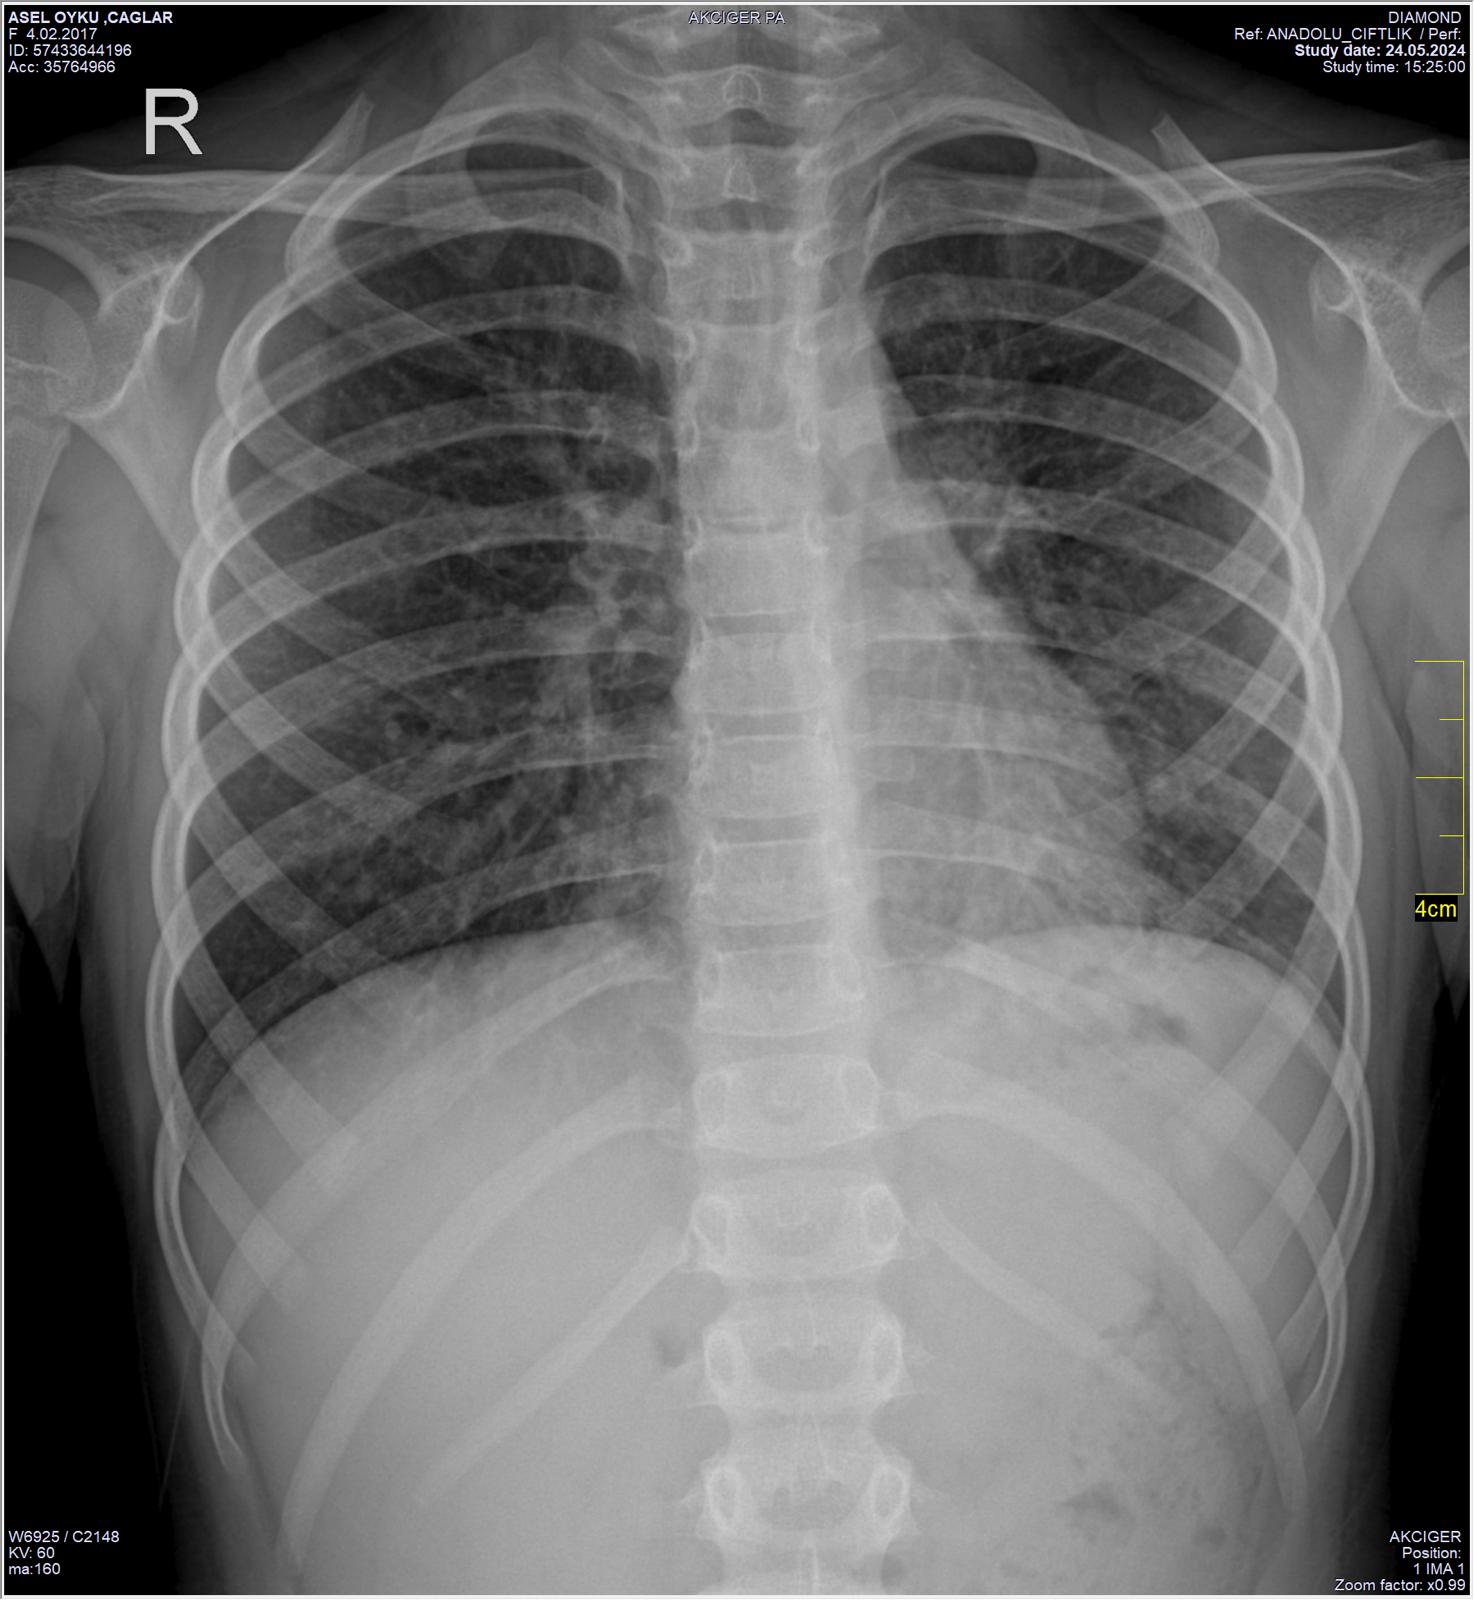

Akciğer Röntgeni HATALI çekilmiş!!

Derin nefes alıp-tutarken çekilmesi gerekirken, akciğerler SÖNÜK iken çekilmiş. Eskiden her Grip hastasına;

astım derlerdi, artık kimse yemediğiği için, "Zatürre" diyorlar!